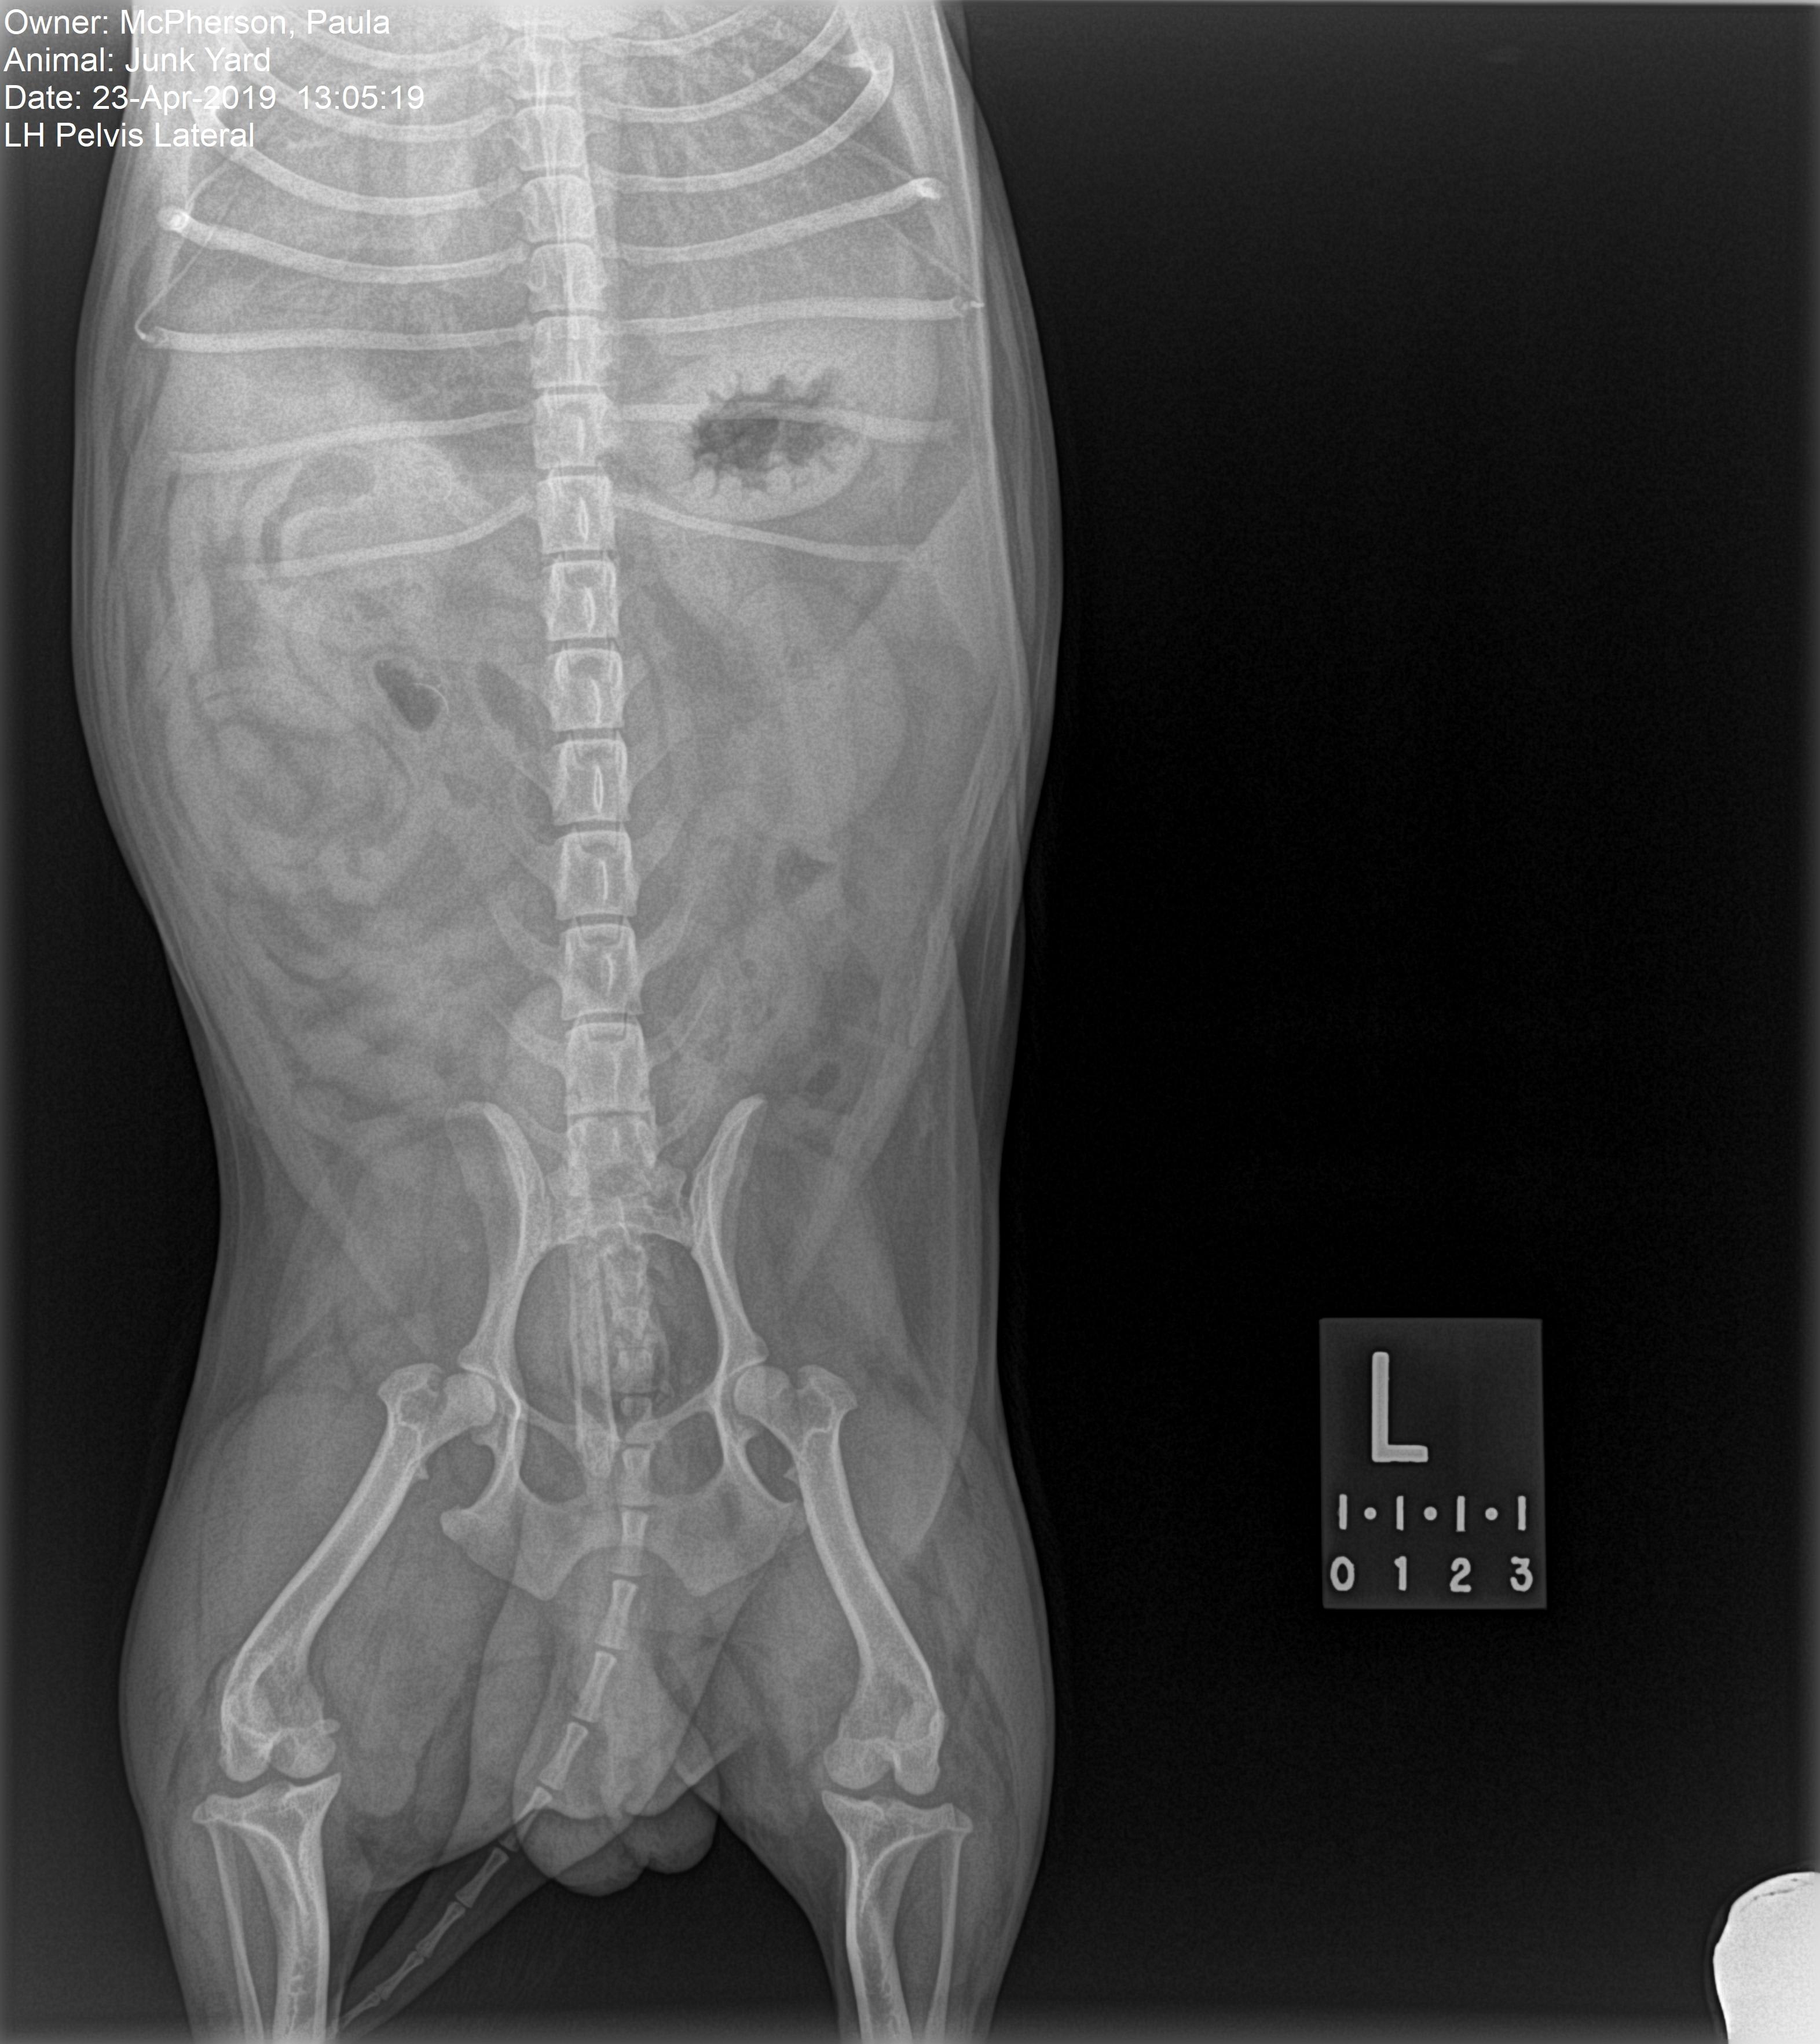

Hello, i have a little maltese cross chui that has been limping for a pbout 8 weeks now. I have seen 3 vets and had xrays done which are Attached . All three have diagnosed something different, fracture to the upper femer bone, soft tissue damage, crutial ligament damage. They all have suggested the same treatment which is complete rest only going out for toilet and back in. Ive noticed anal glands are inflamed and possibly infected. Could this be the reason for his limping. Kind regards paula

No anal gland irritation wouldn't cause limping. Since you're getting so many different opinions, I'd recommend going to an orthopedic specialist if at all possible. If not, try the completely resting and see if that helps.